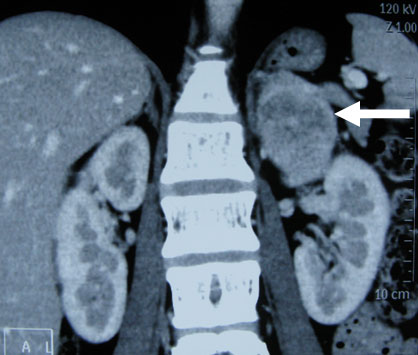

腹腔镜肾癌根治术

腹腔镜切除肾上腺嗜铬细胞瘤